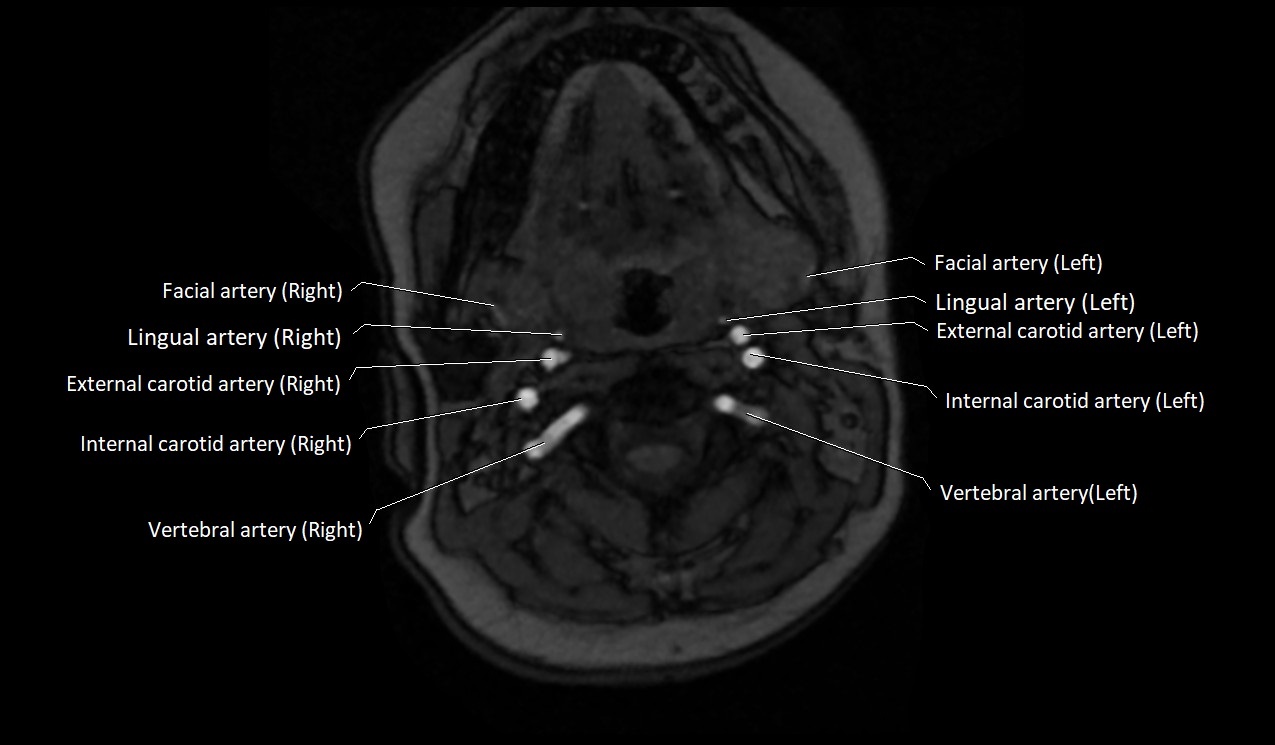

MRI Appearance:

• T1-Weighted Images:

• Appears as a tubular, hypointense (dark) structure relative to muscle

• May show flow void if the blood flow is fast

• T2-Weighted Images:

• Typically hypointense or isointense to muscle, but can be hyperintense if slow flow or stasis is present

MRI images